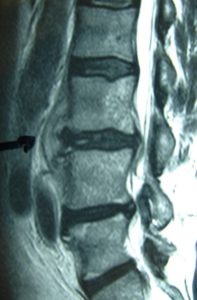

Μαγνητική Τομογραφία-Ακολουθία Τ1 και Τ2 της Ο.Μ.Σ.Σ. γενόμενη προ της εισαγωγής του στις 04/06/2007.

Οβελιαία τομή (α,β). Καταδεικνύεται η εκφύλιση του μεσοσπονδύλιου δίσκου στα επίπεδα Ο3-Ο4, Ο4-Ο5 και Ο5-Ι1 με μικρή οπίσθια προβολή ιδιαίτερα στο επίπεδο Ο3-Ο4. Ωστόσο στο επίπεδο αυτό είναι εμφανής η πρόσθια αποστηματική συλλογή.

Μετωπιαία τομή (γ,δ) Δεν είναι εμφανής η ύπαρξη της αποστηματικής συλλογής ωστόσο στο επίπεδο Ο3-Ο4 (Α) πιθανολογείται η ύπαρξη μάζας η οποία προκαλεί απώθηση του υοϊτού μυός.

Εγκάρσια τομή (ε,ζ) Είναι σαφής η ύπαρξη προ και παρασπονδυλικής αποστηματικής συλλογής και σε μικρότερο βαθμό οπισθίως εντός του σπονδυλικού σωλήνα.